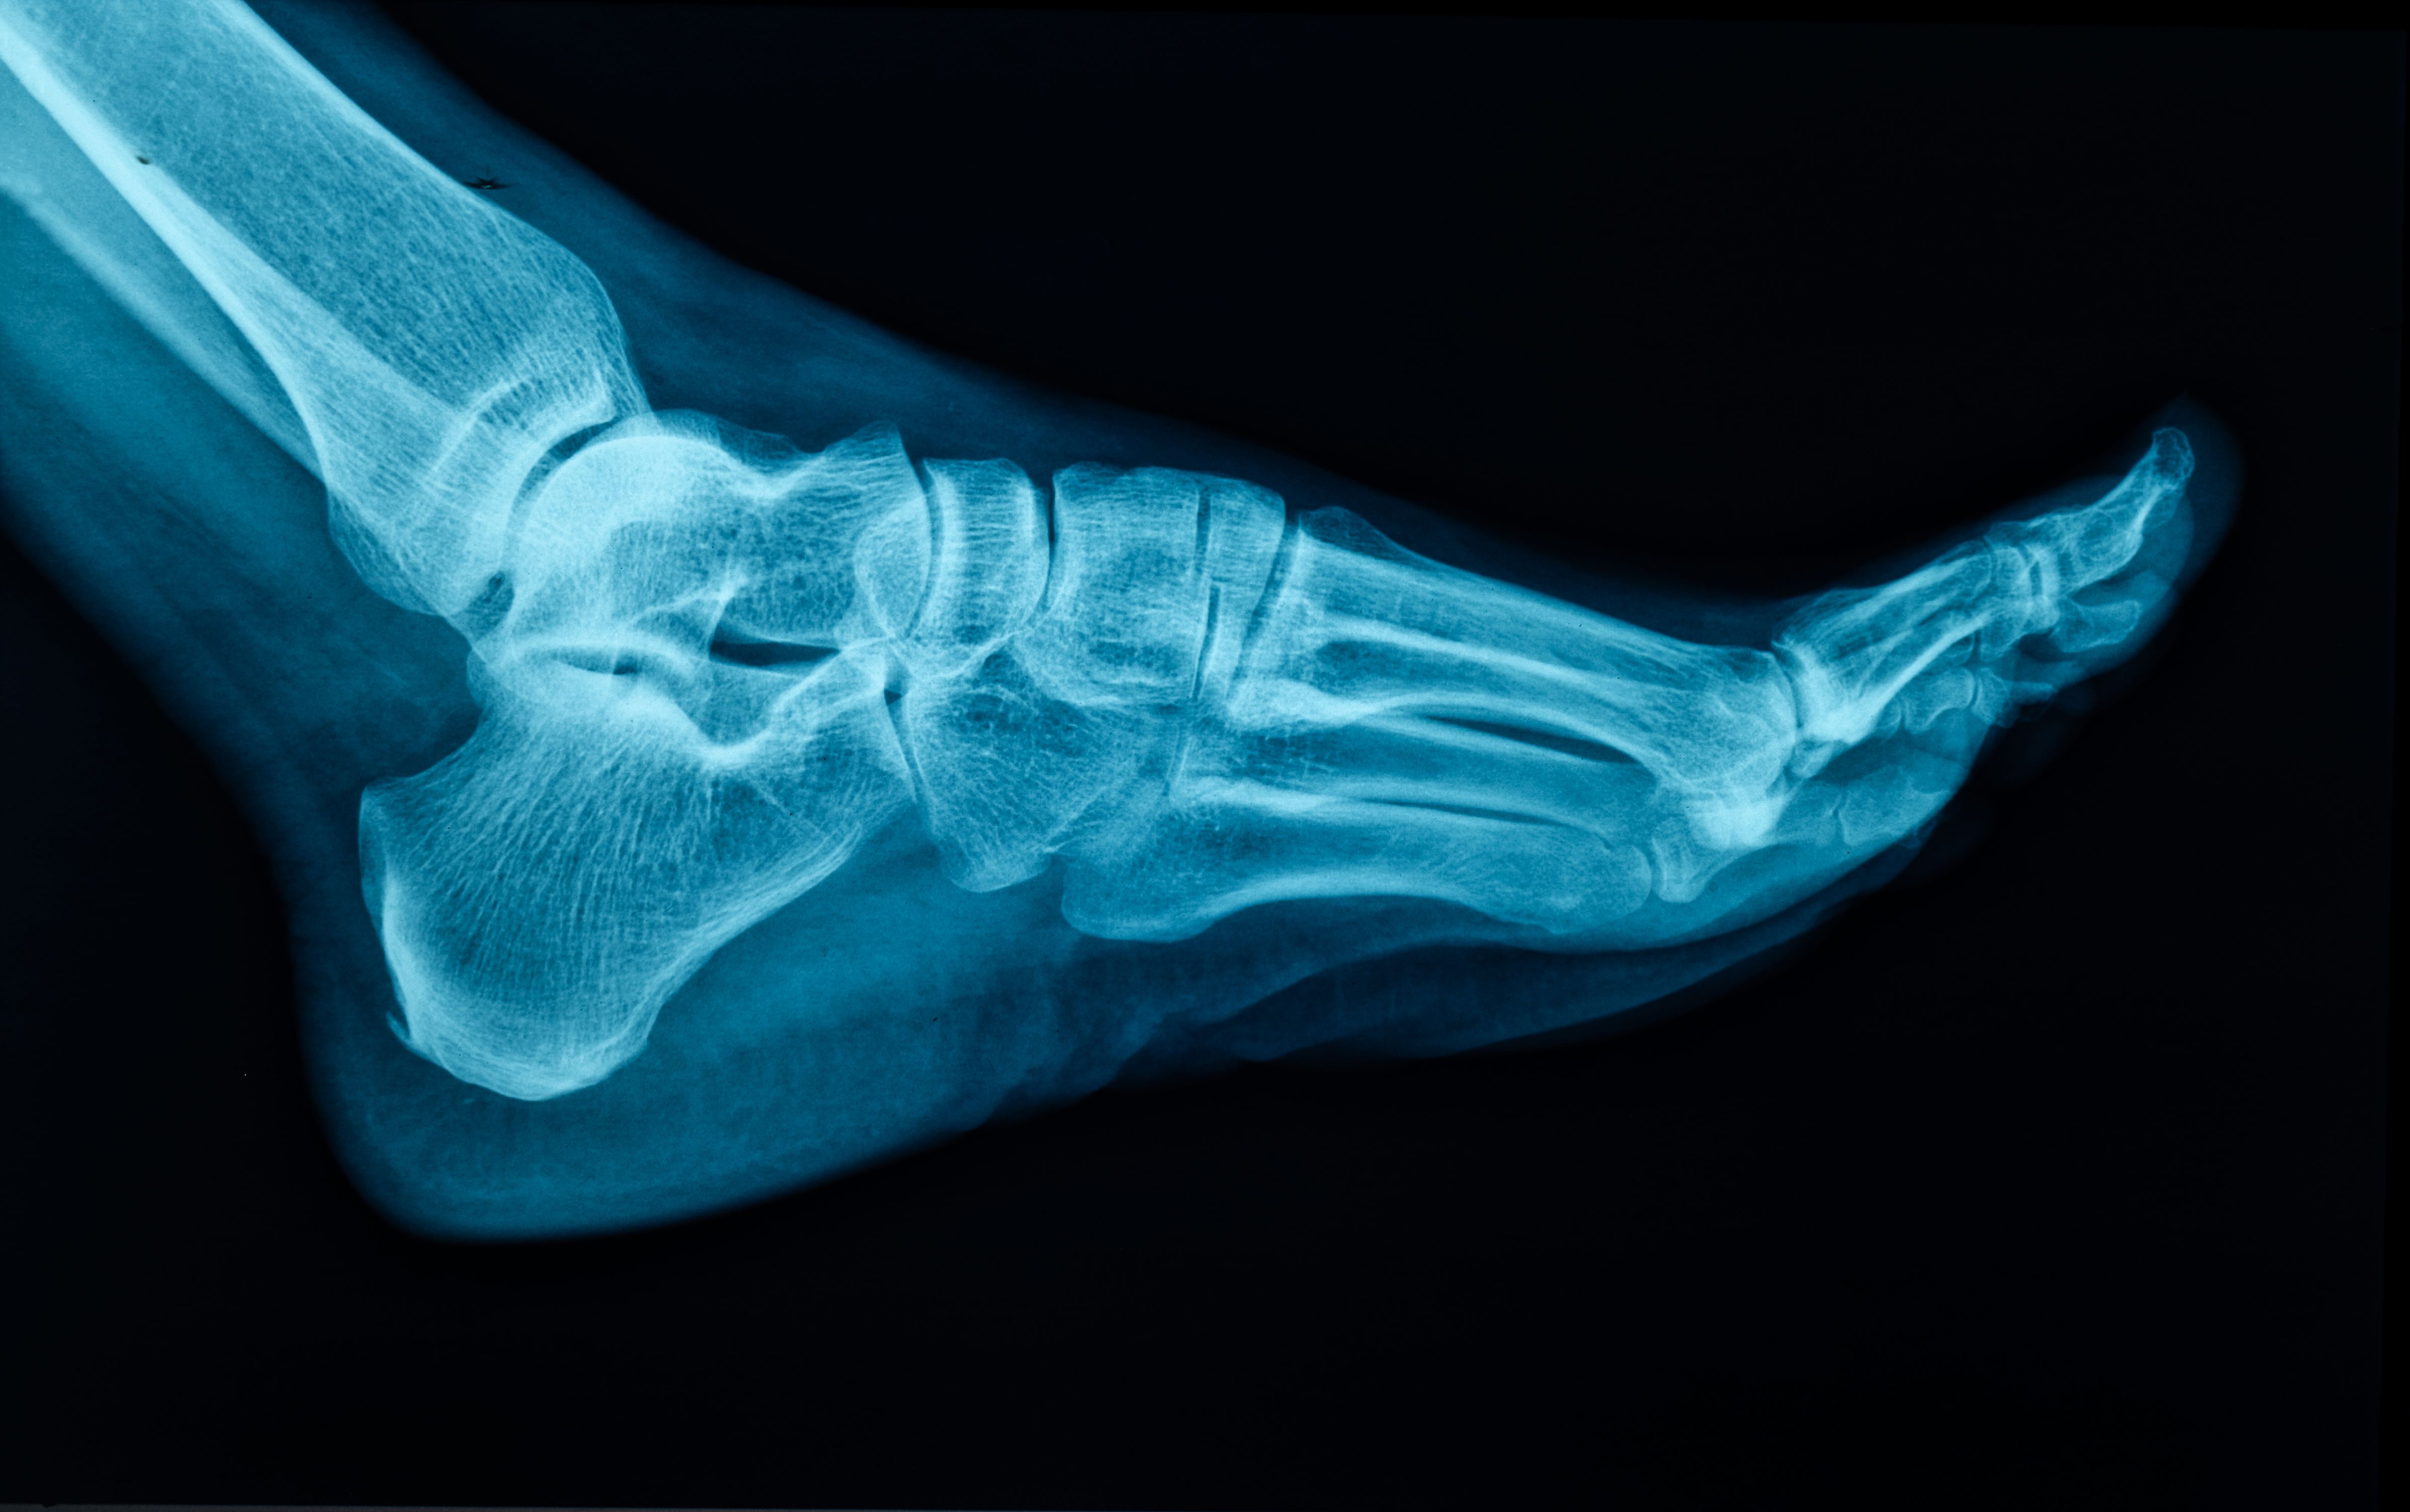

- Imaging Tests: X-rays, MRI, or CT scans provide detailed insights into bone and soft tissue conditions.